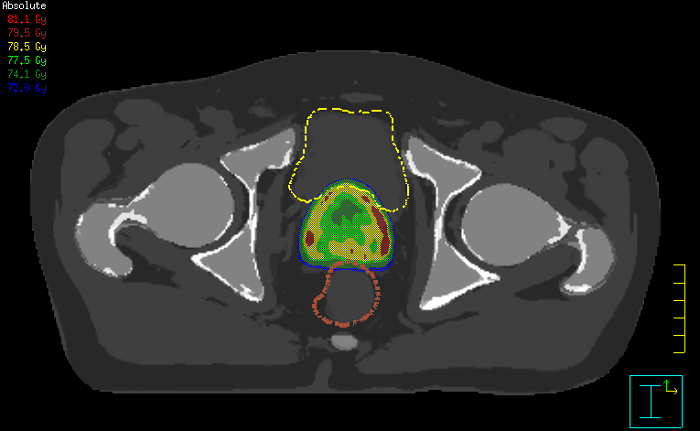

With its exceptional soft-tissue visualization capabilities and wide range of image contrasts, MRI has become a powerful tool to help more precisely define tumor boundaries. This is particularly important as it has been established that there is a high degree of uncertainty in target volume delineation, and it is even reported to represent the largest uncertainty in the entire radiotherapy process for most tumor sites**. Better visualization of the target area and nearby organs-at-risk is a key factor in enhancing target volume delineation. MRI’s expanding role also can be attributed to its functional imaging capabilities, which can inform both target characterization and treatment response.

The ability to tune contrasts can provide even more valuable information about tumor characteristics and tumor extent to facilitate enhanced delineation, and also provides possibilities for dose boosting strategies.

Innovative strategies in MRI-only simulation have made it possible to derive CT-like electron density information from MR imaging data. This capability enables physicians to use MRI as the radiotherapy department’s primary imaging modality for specific applications to eliminate tedious and error-prone CT-MR registration and simplify workflows.

Our innovative MRCAT (MR for Calculating ATtenuation) clinical applications lets you plan radiation therapy using MRI as primary imaging modality. Within just one, fast MR exam, MRCAT provides both excellent soft-tissue contrast for target and OAR delineation and CT-like density information for dose calculations.